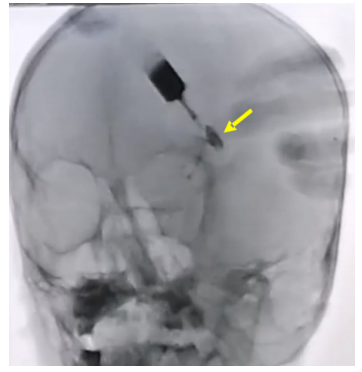

初步诊断:1)左眼先天性泪腺皮肤瘘;2)左眼上睑毛发异位。患儿病情复杂,为明确诊断,为患儿行在全身麻醉下行左眼泪腺瘘管数字减影检查,结果显示左眼泪腺瘘管造影剂存留,瘘管深部存在扇形腔隙(图2)。并行泪腺瘘管CT造影检查,行眼眶CT水平+冠状位扫描,泪腺瘘管CT造影结果显示左眼外侧泪腺高密度影(图3)。后予患儿全身麻醉下行左眼泪腺皮肤瘘管探查+异位毛发病灶切除+泪腺瘘管转位结膜囊吻合代泪腺导管术。患儿取仰卧位,全身麻醉起效后,常规用75%酒精消毒左眼周围皮肤,铺无菌手术巾。自泪腺瘘管皮肤面注入亚甲蓝标记瘘管,瘘管内插入冲洗针,翻转眼睑,暴露穹隆结膜,冲洗针引导下横行切开穹隆结膜3 mm。沿左上睑瘘口周围做梭形皮肤切口,钝性分离瘘管周围组织,术中发现瘘管基底部呈扇形,内表层为上皮组织,见毛囊及较多毛发,且有一大小约为3 mm×3 mm×2 mm的异位泪腺组织,其与瘘管相连,瘘管的另一端与正常泪腺导管相连。完整切除皮肤到异位泪腺之间的瘘管和异位泪腺及异位毛发病灶,切除的病变组织(图4)送病理检查。将正常泪腺导管用8/0可吸收线固定缝合于颞上穹隆结膜,导管内置引流条1根,引流条以8-0线固定缝合于睑结膜表面,6-0丝线间断缝合皮肤切口。术毕,予患儿左眼戴角膜绷带镜,绷带加压包扎左眼。手术顺利,切口愈合好,术后2 d打开加压包扎(图6)观察,患儿左眼上睑皮肤无明显红肿,无渗血、渗液,切口对合好,缝线在位,泪腺导管引流条在位,术后 7 d 拆除缝线,取出泪腺导管引流条。术后病理报告确诊左眼先天性泪腺皮肤瘘管伴毛发异位,异位泪腺(图5)。患儿于2022年9月22日出院。术后1个月返院复查,结膜吻合口和皮肤切口愈合好(图7),转位的泪腺瘘管成功将泪液引流入上穹隆结膜囊内。术后随访1年,未见瘘管复发。

图 2 左眼泪腺瘘管数字减影检查

Figure 2 Digital subtraction imaging of the lacrimal fistula in the left eye

左眼泪腺瘘管造影剂存留,瘘管深部存在扇形腔隙(黄色箭头)。It showed that contrast media remained and there were fan-shaped spaces in the depth of the fistula(yellow arrow).